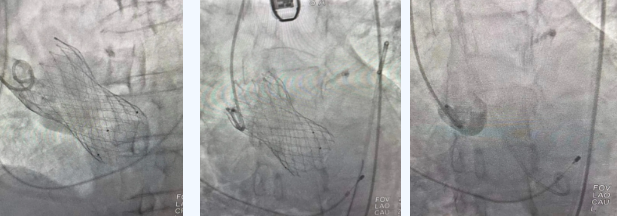

在麻醉手術(shù)中心的配合下,曾廣偉主任用導(dǎo)管經(jīng)股動(dòng)脈鞘進(jìn)入主動(dòng)脈瓣目標(biāo)位置,經(jīng)豬尾導(dǎo)管造影可見(jiàn)主動(dòng)脈瓣大量返流,因左室流出道較寬,大于瓣膜落腳點(diǎn)直徑,瓣膜釋放位置選擇及釋放難度極大。更為關(guān)鍵的是,患者常規(guī)四個(gè)錨定點(diǎn)只有一個(gè)可以用,定位要極其精準(zhǔn)才能保證瓣膜釋放后牢靠,同時(shí)不能有大的殘余瘺!稍有移位可能就需要再次植入瓣中瓣或者開(kāi)刀!

術(shù)中,曾廣偉主任團(tuán)隊(duì)高效配合,完成了特定時(shí)間點(diǎn)起搏心臟、臨時(shí)短時(shí)間關(guān)閉呼吸機(jī)、降低主動(dòng)脈瓣阻力、快速釋放瓣膜等一系列高難度操作,有效保證瓣膜精準(zhǔn)釋放。瓣膜釋放經(jīng)TEE確認(rèn),主動(dòng)脈瓣膜釋放位置佳,經(jīng)豬尾導(dǎo)管造影,主動(dòng)脈瓣返流即刻消失,且無(wú)瓣周瘺。